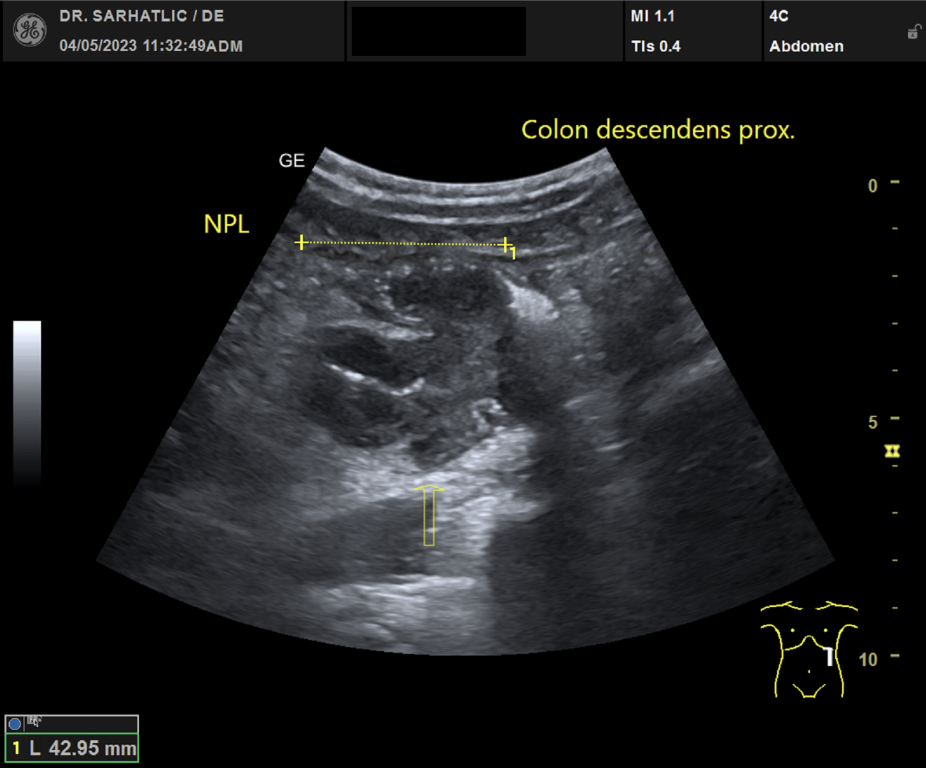

MODERNE ULTRASCHALLDIAGNOSTIK- Modernes Farbdoppler-Ultraschallgerät

- Hochauflösende Schallköpfe

- Detaillierte Organuntersuchungen

- Ultraschall aller inneren Organe (z. B. Leber, Bauchspeicheldrüse, Nieren, Prostata, Schilddrüse)